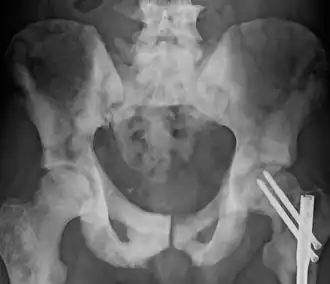

| Pelvis com esclerose causada por metástase. | |

Osteosclerose é o aumento anormal da densidade ósseo,[1] devido à substituição de osso trabecular (saudável) por osso compacto, mais pesado, menos maleável e atrofiando a medula óssea. Pode ser detectada por uma radiografia simples por uma marcada opacidade. É um sintoma de muitas doenças diferentes, algumas hereditárias e outras adquiridas.